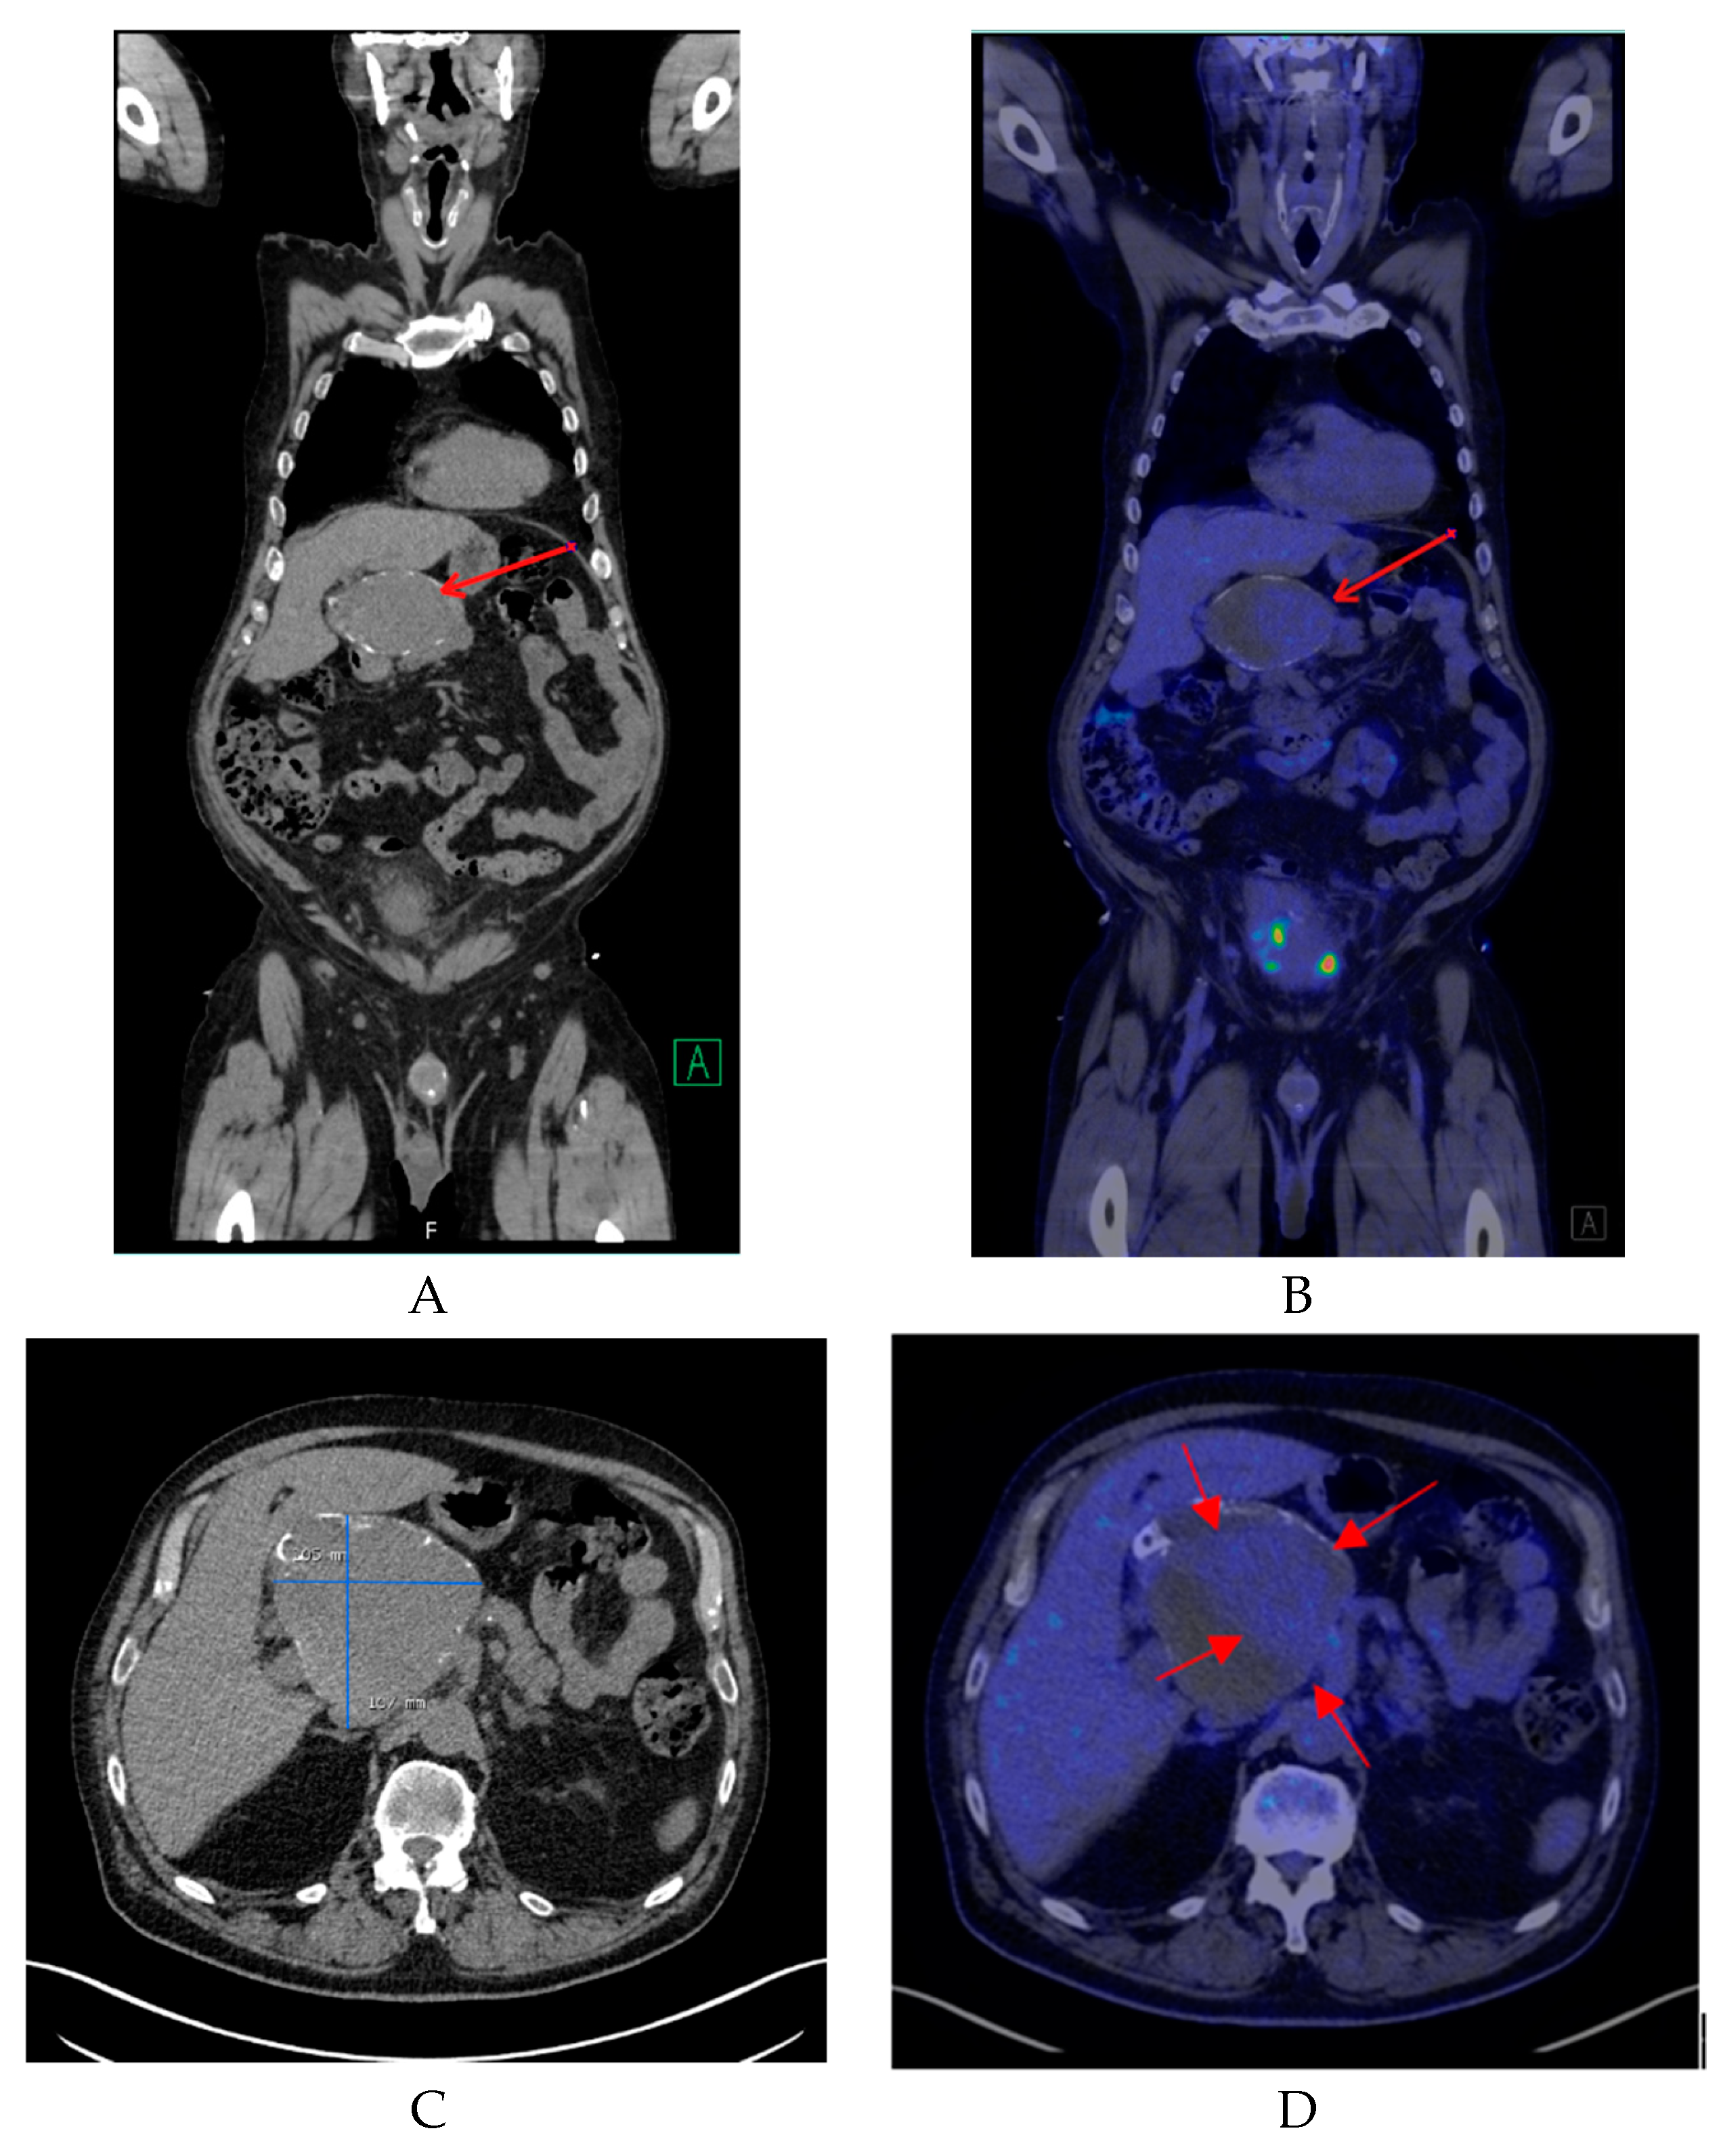

2. Case Report